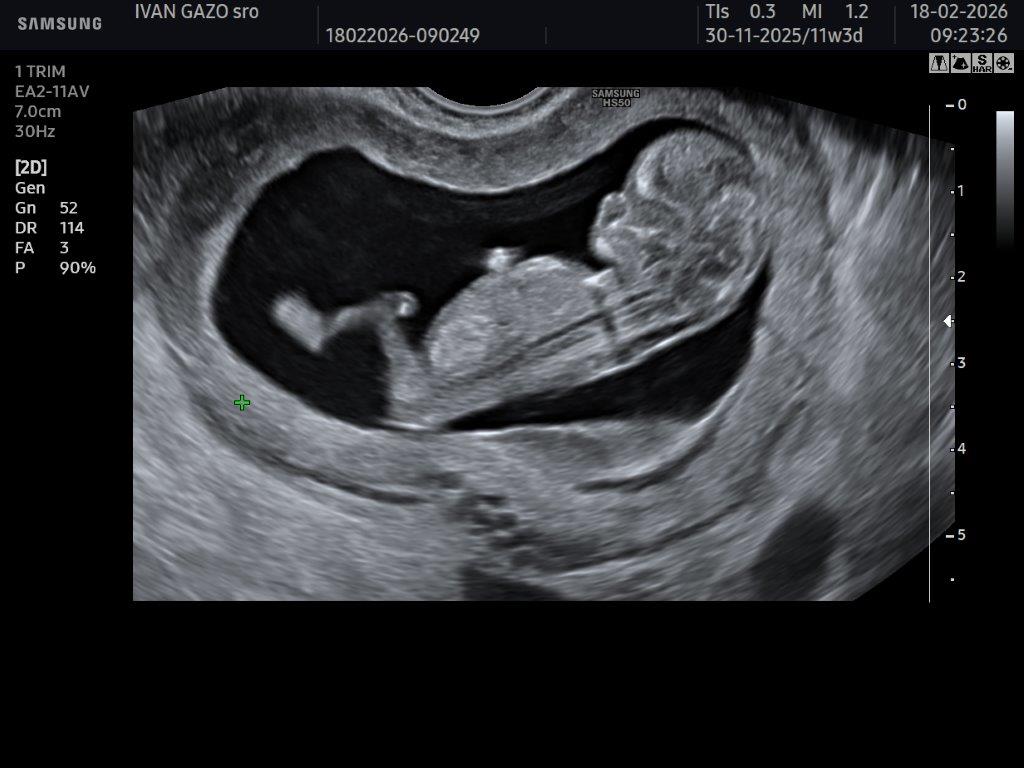

- Ultrazvukové vyšetrenia: vo včasnej gravidite diagnostika tehotnosti,overenie lokalizácie v maternici a životaschopnosti tehotnosti. V priebehu gravidity 3 skríningové vyšetrenia: 12-13 týždeň,20-22 týždeň,30-32. týždeň možnosťou tlačenej fotografie, event. 3D/4D záznamu na prinesený USB kľúč. Vyšetrenie optimálne v 24-28t. tehotnosti pri dobrej vizualizácii plodu.